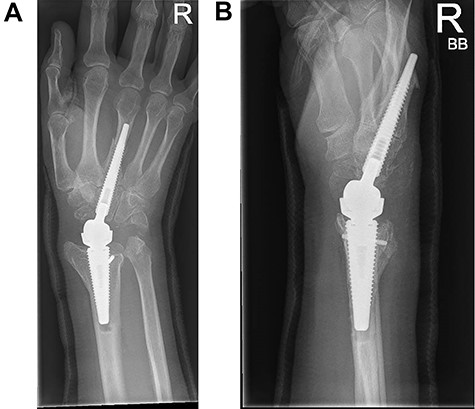

Following appropriate consultation and consent, she underwent total wrist arthroplasty. She reported complete pain relief and an improved range of movement. Ten weeks following surgery the patient presented in the emergency department following a fall. She landed heavily on the dorsiflexed hand and wrist, immediately noticing a change. Imaging confirmed that she had sustained a periprosthetic fracture in the middle finger metacarpal with dorsal displacement of the implant (Fig. 2A and B). Following a trial of non-operative treatment, she underwent revision surgery. The distal metacarpal implant was removed and replaced with a longer implant and the metacarpal fracture defect region was reinforced with autologous bone graft (Fig. 3A and B).

(A and B) PA and lateral radiographs following revision surgery to a longer metacarpal implant.

Three months following surgical treatment of her periprosthetic fracture, when reviewed in the outpatient clinic, the fracture had united and she demonstrated an excellent range of pain free motion and improved wrist function reflected in an improved PRWHE score from 66 preoperatively to 22, 3 months after surgery.